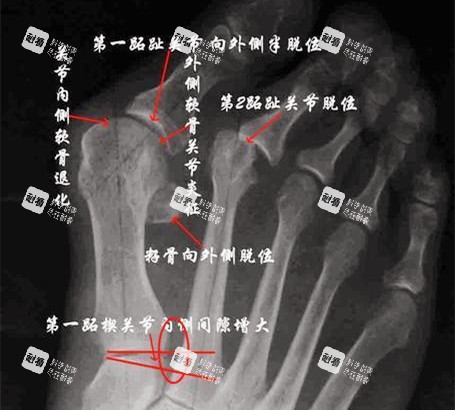

看片:盯著X光片講:“你這跖骨內翻15度,得截骨調整到5度以內,不然容易復發(fā)!”

負重位X光片:站著拍,看清骨骼受力時的變形程度!